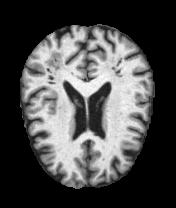

MRI Brain Scans Dataset - All Categories

Moderate Dementia

Severe tissue loss

Real MRI scans showing progressive structural brain changes across all dementia stages

- • Total Images: 6,400+ brain scans

- • Normal Cognition: 3,200 cases

- • Very Mild Dementia: 2,240 cases

- • Mild Dementia: 896 cases

- • Moderate Dementia: 64 cases